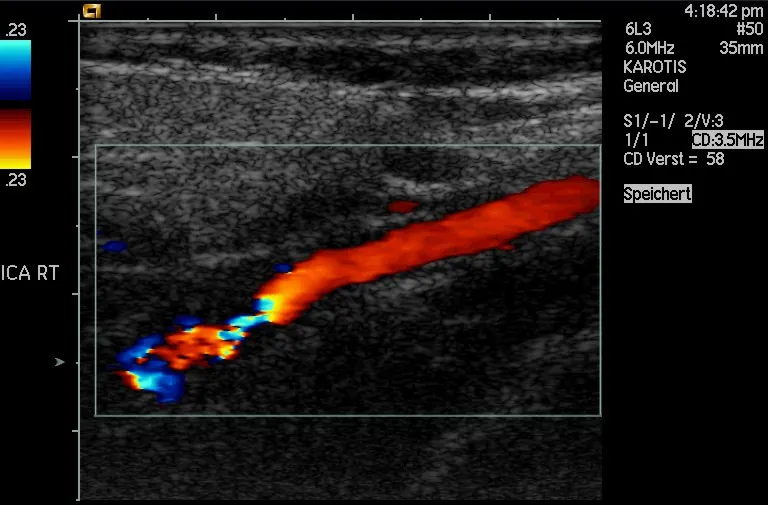

Another major use of ultrasound in medical diagnostics is to detect motion and determine velocity through the Doppler shift of an echo, known as Doppler-shifted ultrasound. This technique is used to monitor fetal heartbeat, measure blood velocity, and detect occlusions in blood vessels, for example. (See Figure 17.45.) The magnitude of the Doppler shift in an echo is directly proportional to the velocity of whatever reflects the sound. Because an echo is involved, there is actually a double shift. The first occurs because the reflector (say a fetal heart) is a moving observer and receives a Doppler-shifted frequency. The reflector then acts as a moving source, producing a second Doppler shift.

Doppler-shifted ultrasonic image of a partially occluded artery.

Figure 17.45 This Doppler-shifted ultrasonic image of a partially occluded artery uses color to indicate velocity. The highest velocities are in red, while the lowest are blue. The blood must move faster through the constriction to carry the same flow. (credit: Arning C, Grzyska U, Wikimedia Commons)